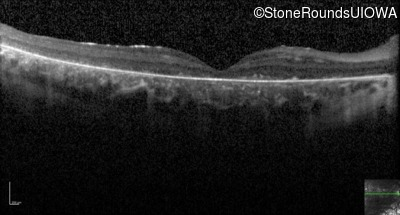

Optical Coherence Tomography - Right - 5/200

Exemplar / OCT Stack